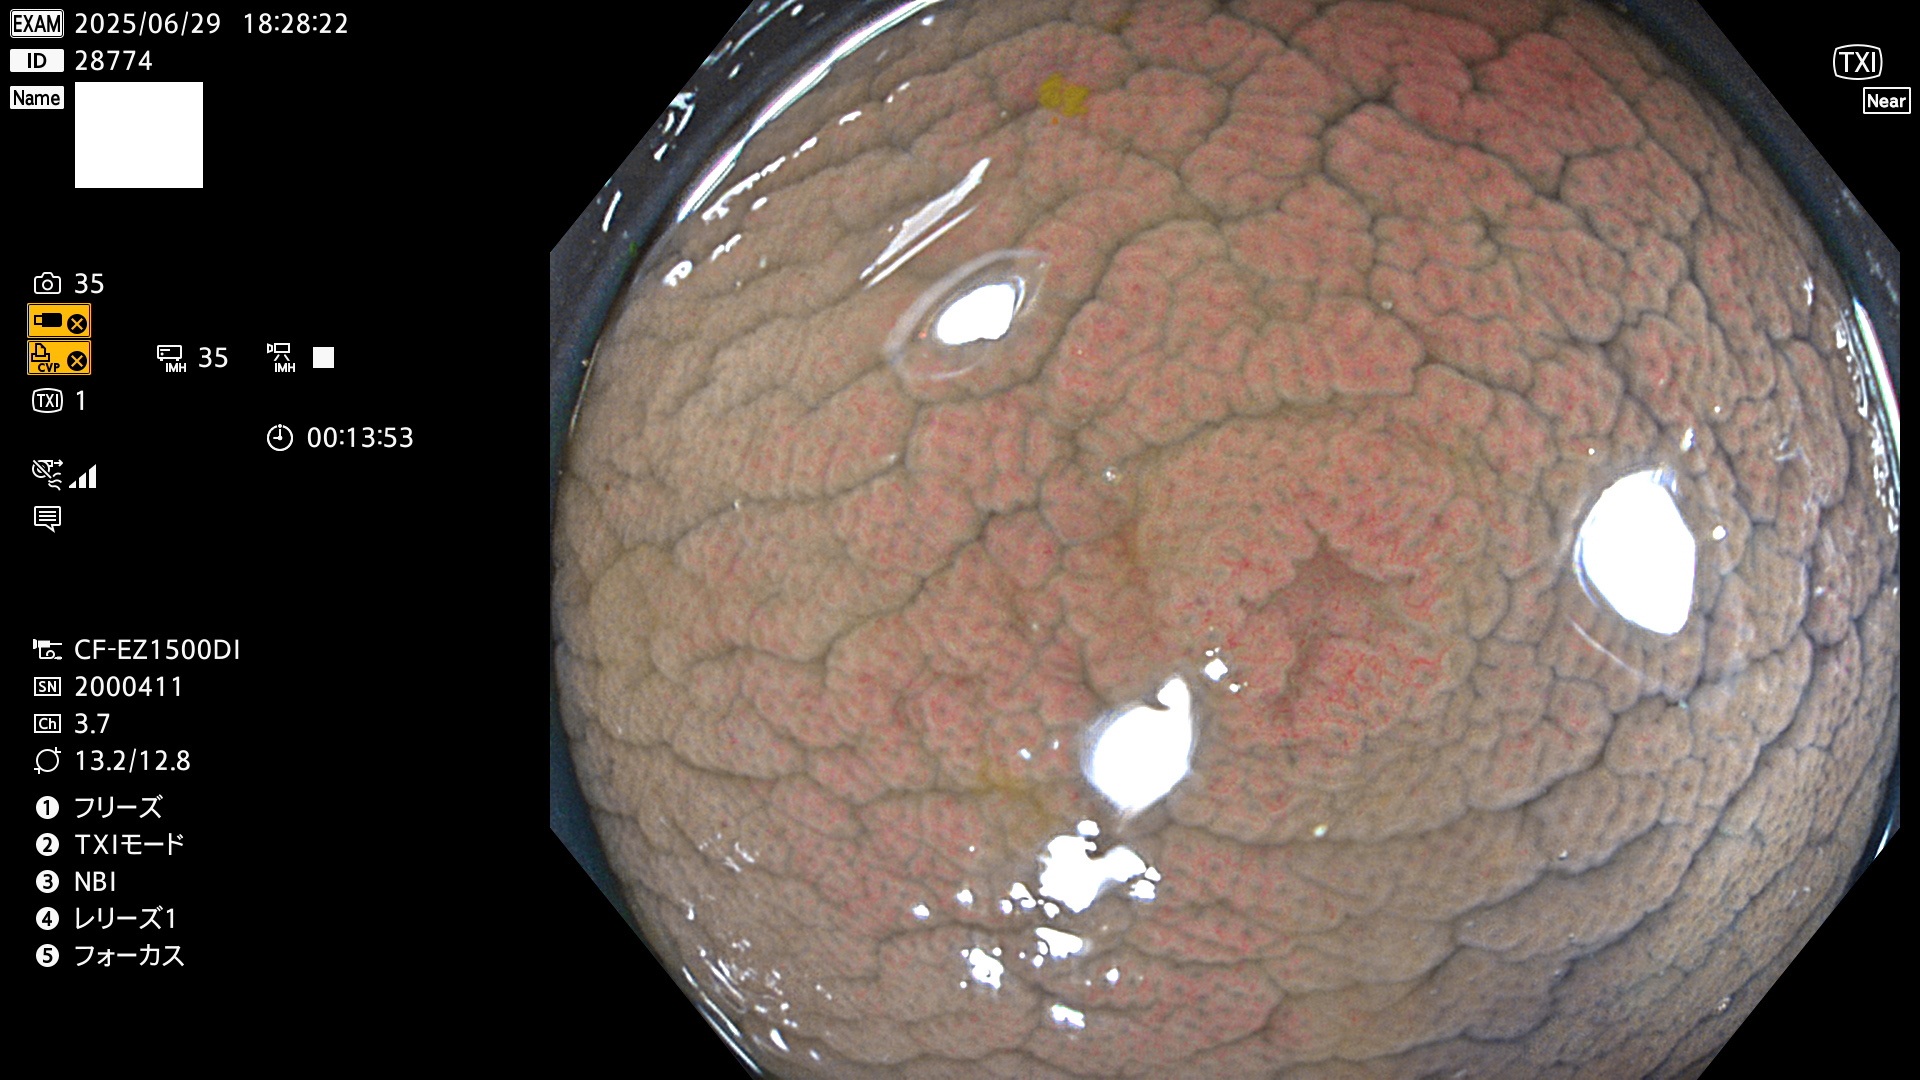

今週のUb、Uc型腺腫

完全に平坦な物をUb、陥凹している物をUcと呼びます。Ubは認識が困難で、Ucはびらん(炎症)と紛らわしいために見落とされやすく、「内視鏡後・大腸癌」の原因になります。

毎週の検査(木・金・土・日)に発見されたUb、Uc型・腺腫を、その週の日曜の夜にUPし1週間、提示します。

抽出の対象期間 2025年6月26日〜6月29日の4日間(40件の検査)7個 (7/40=18%)